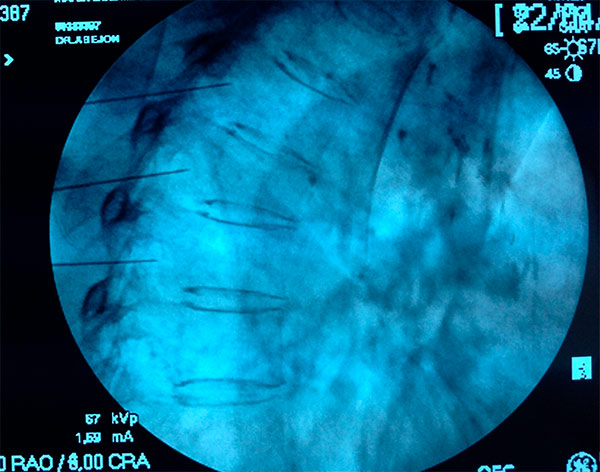

Paciente en decúbito prono con una almohada bajo el tórax. Con arco de fluoroscopia Rx en AP se debe identificar el cuerpo vertebral de T2, a continuación se debe girar el arco aproximadamente 20º para conseguir una buena alineación del ángulo costovertebral y 10-20º en dirección craneal para eliminar el doble contorno. El punto de entrada está en el borde lateral de la parte inferior de T2, por encima de la cabeza de la tercera costilla. Se infiltran los planos con anestésico local y se introduce un Abocth® del 16 en visión túnel unos 2-3 cm y a través del mismo se introduce la aguja de radiofrecuencia curva de 10cm calibre 22G y punta roma con la curva en dirección al cuerpo vertebral, lo más próximo posible al borde lateral de T2 en el arco de fluoroscopia en Rx AP. En la proyección lateral se verifica la profundidad de la aguja que debe quedar en la mitad del cuerpo de T2, se inyectan 1-2ml de contraste que debe fluir craneocaudalmente y se procede a la estimulación.

Estimulación sensoria: (50Hz) a un voltaje de 0.4-0.6v, no debiendo existir estimulación sensitiva de los nervios intercostales.

Estimulación motora: (2Hz) con un voltaje superior a 1v no debiendo existir estimulación motora de los intercostales. Posteriormente se inyecta 1ml de lidocaína al 2% y se hace la lesión a 80º durante 90 segundos.

Esta misma técnica se realiza posteriormente en T3.